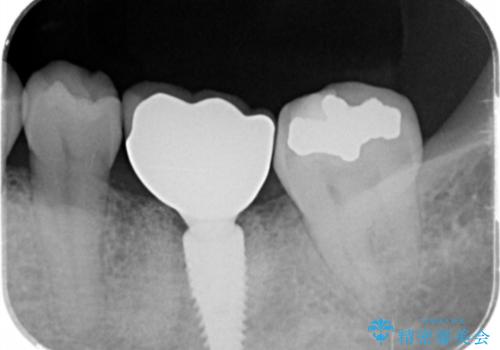

- 「歯がぐらぐらして噛めない、歯を抜いて欲しい、またしっかりと噛めるようになりたい。」、と歯周病治療を希望され来院されました。

歯の根本まで骨吸収が進み、ぐらぐらになってしまった歯を抜去し骨の造成を行ったのちインプラント治療を計画します。

重度に吸収してしまった歯槽骨をしっかりと造成を行ったのちにインプラント治療を行ったので、安定した歯周環境にすることができました。